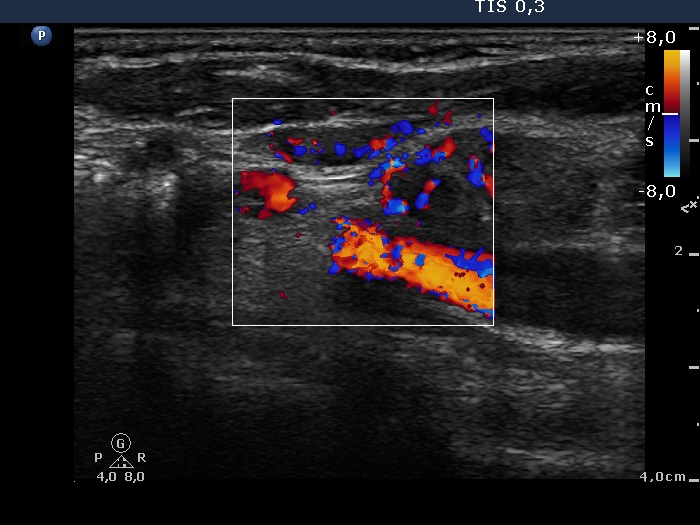

Ultrasonography. The thyroid was echonormal and contained multiple nodules. The right lobe was composed of an echonormal and a cystic nodule. A large moderately hypoechogenic nodule occupied almost the entire left lobe. It had irregular borders, was lobulated and displayed microcalcifications and intranodular vascularization. There were multiple enlarged lymph nodes in the left side of the neck.

Cytology. Papillary cancer was diagnosed in the nodule in the left lobe and a metastasis of the thyroid cancer into one of the enlarged lymph nodes.